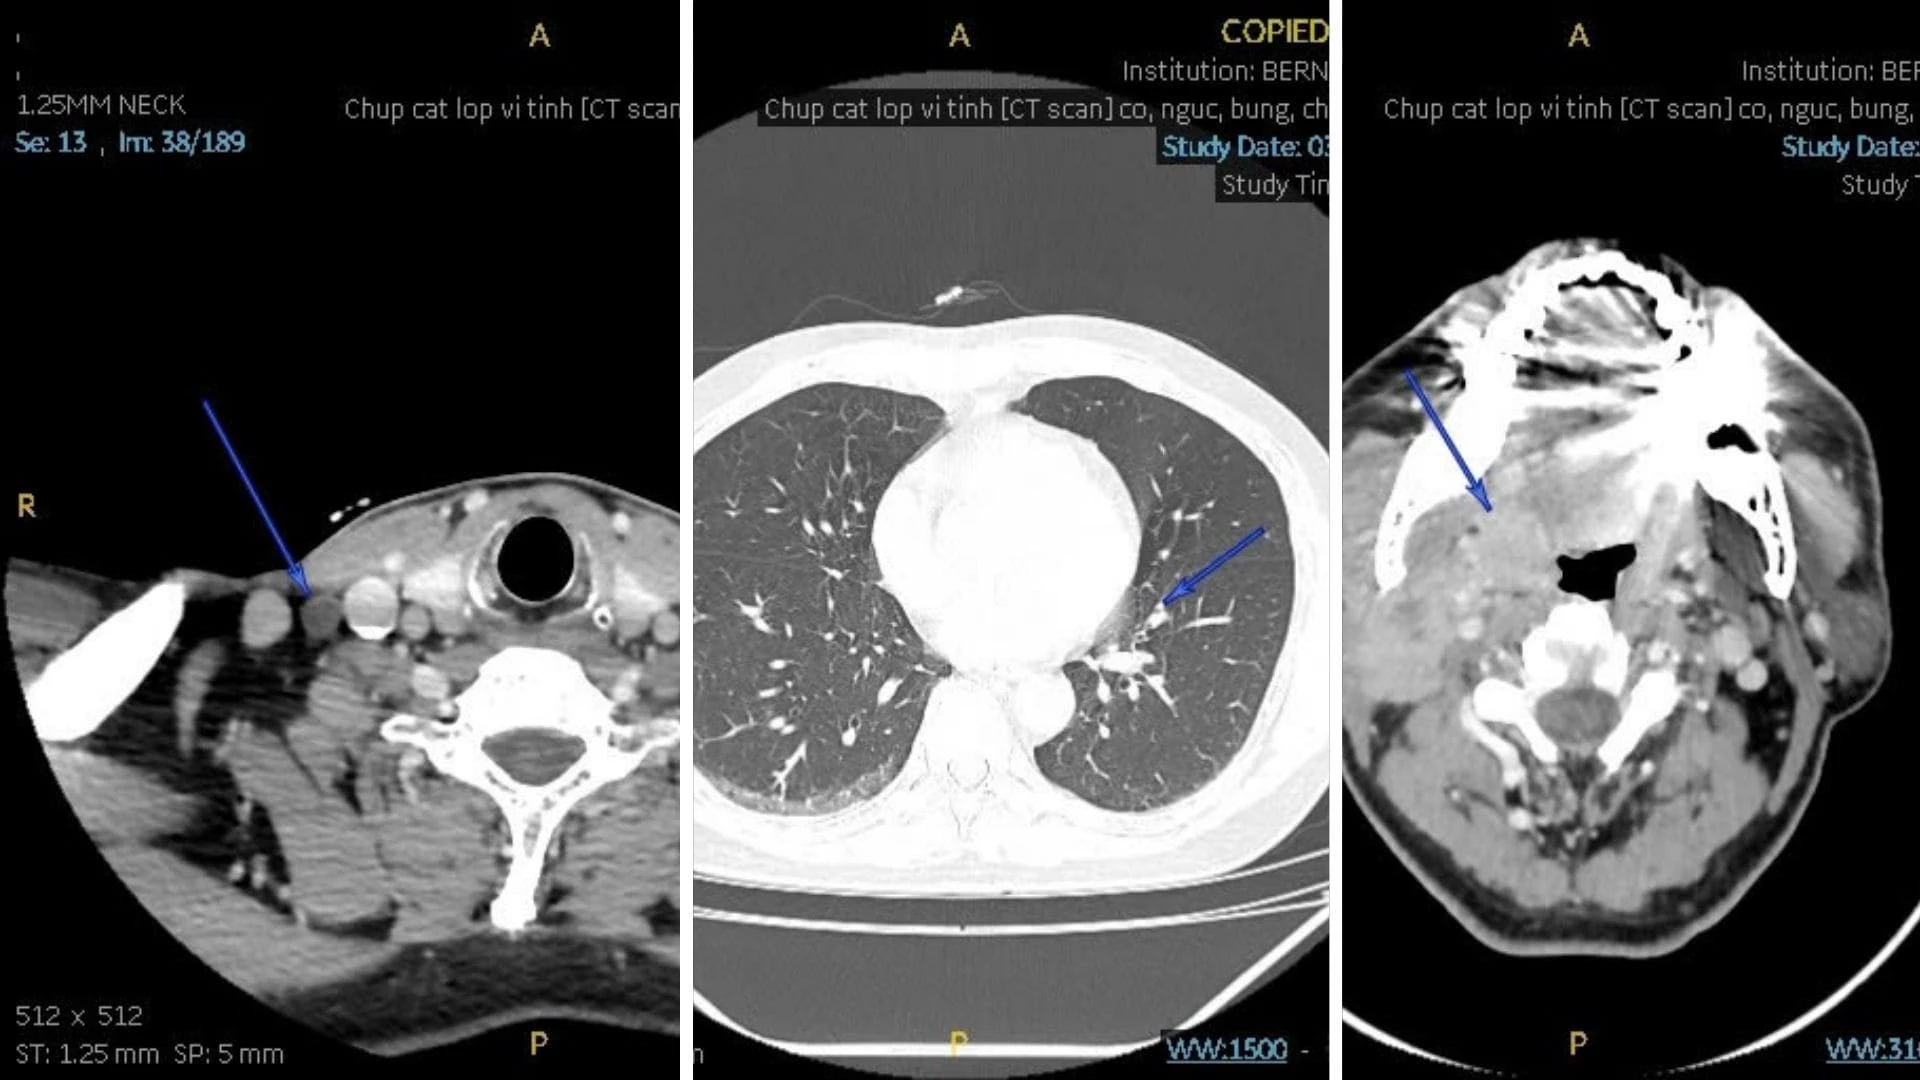

| Hình ảnh CT Scan ghi nhận tổn thương choán chỗ vùng amidan phải và hạch cổ lớn (Ảnh: Hệ thống PACS Bernard) |

Kết quả CT Scan ghi nhận có khối choán chỗ khẩu hầu mức amygdale (phải), kích thước 1,9 x 2,1 cm, bờ không đều, bắt quang trung bình, nghi ngờ u ác và hạch lớn khoang cảnh phải (2 x 2,9 cm), bắt quang không đồng nhất, có hoại tử. Những đặc điểm này gợi ý tổn thương đã di căn hạch cổ.

Các cơ quan tim, phổi, gan-thận không ghi nhận bất thường ác tính, chỉ có một số tổn thương xương cũ và thoái hóa cột sống đi kèm.

Kết luận từ chuyên gia chẩn đoán hình ảnh Bernard là tổn thương choán chỗ amidan phải kèm hạch lớn vùng cổ phải, phù hợp phân loại T2N1Mx (giai đoạn III). Điều này cho thấy khối u đã lan đến hệ bạch huyết vùng cổ - tức đã có di căn hạch vùng.